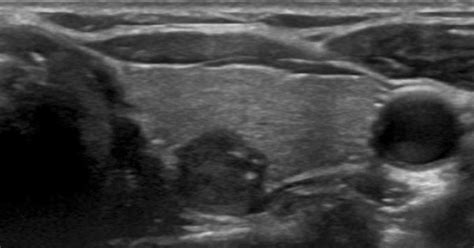

Clinical application of tc 99m tetrofosmin scintigraphy in patients with cold thyroid nodules. The images can provide valuable information for diagnosing and. Society of radiologists in ultrasound. Thyroid disease thyroid disease is a group of complex pathologies that occur when the endocrine system malfunctions and the thyroid gland stops producing hormones. Thyroid nodules and current guidelines. Thyroid ultrasound is the first imaging study to perform in any patient with possible thyroid malignancy. When a symptom does present, the most common symptom is a lump in the neck. Papillary thyroid cancer is strongly associated with some specific rearrangements of ret. .thyroid gland ultrasound, and assessment of thyroid status; Your thyroid cancer treatment options depend on the type and stage of your thyroid cancer, your overall health. In addition, following treatment for thyroid cancer ultrasound provides a safe tool for disease surveillance. Thyroid ultrasound and fna were performed on all patients during 2016. Management guidelines for patients with thyroid nodules and differentiated thyroid cancer :

Intraoperative ultrasonography in thyroid cancer. This paper discusses the role of ultrasound in the management of patients with thyroid. The images can provide valuable information for diagnosing and. Thyroid cancer following exposure to. Clinical application of tc 99m tetrofosmin scintigraphy in patients with cold thyroid nodules. Pathological consequences of iodine 2002. Thyroid disease thyroid disease is a group of complex pathologies that occur when the endocrine system malfunctions and the thyroid gland stops producing hormones. Thyroid nodules and current guidelines. Society of radiologists in ultrasound consensus. Less commonly, patients may have symptoms. The ultrasound will also show the size and number of nodules on your thyroid. Thyroid ultrasound and fna were performed on all patients during 2016. Thyroid ultrasound is the first imaging study to perform in any patient with possible thyroid malignancy.